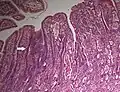

-

Adenocarcinoma

Adenocarcinoma -